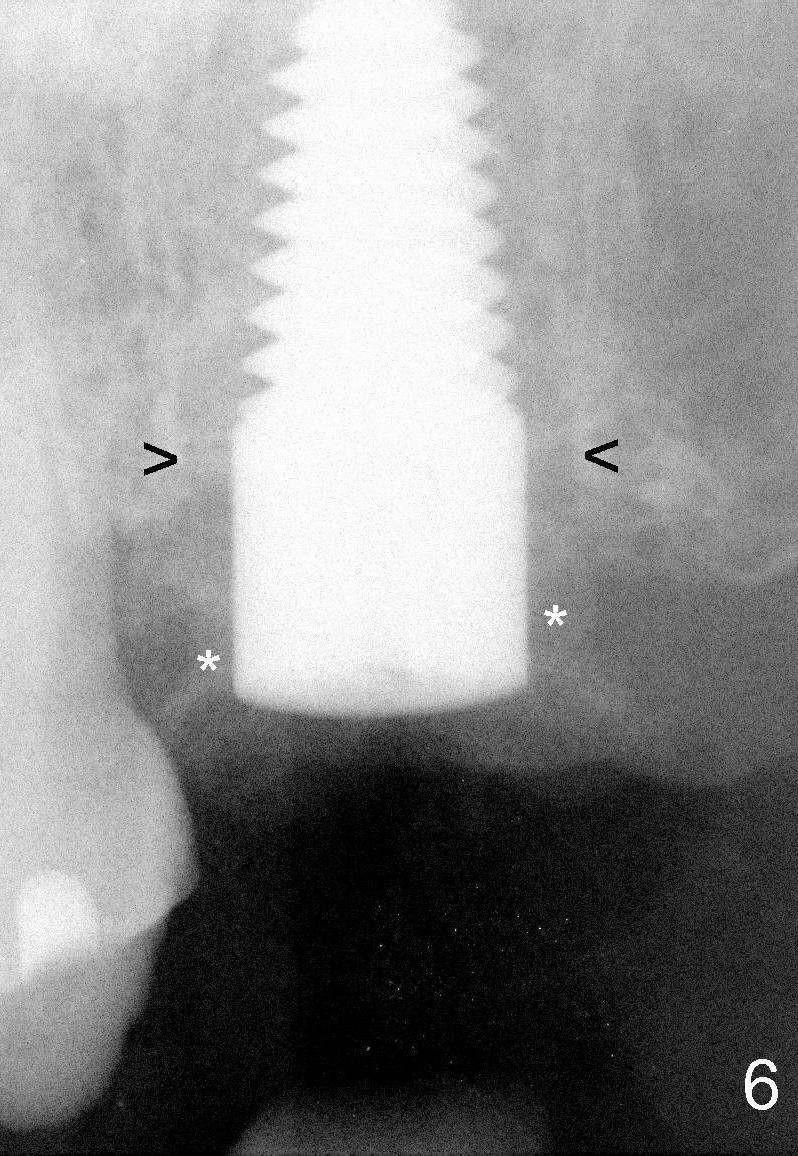

Fig.6: 6x20 mm implants (*: bone graft).